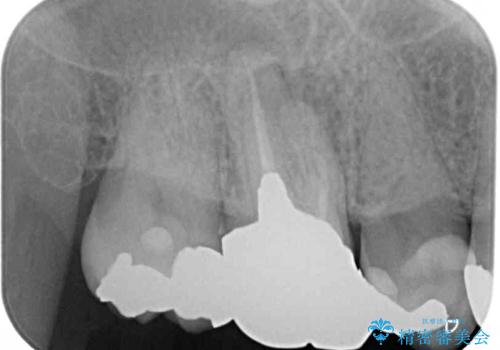

小臼歯は根管治療後に痛みが引きましたが、隣の大臼歯の痛みは引かなかったため、大臼歯も根管治療を行いました。

根管治療後に痛みは引き、半年後のレントゲン写真では根尖の病変の消失が認められました。